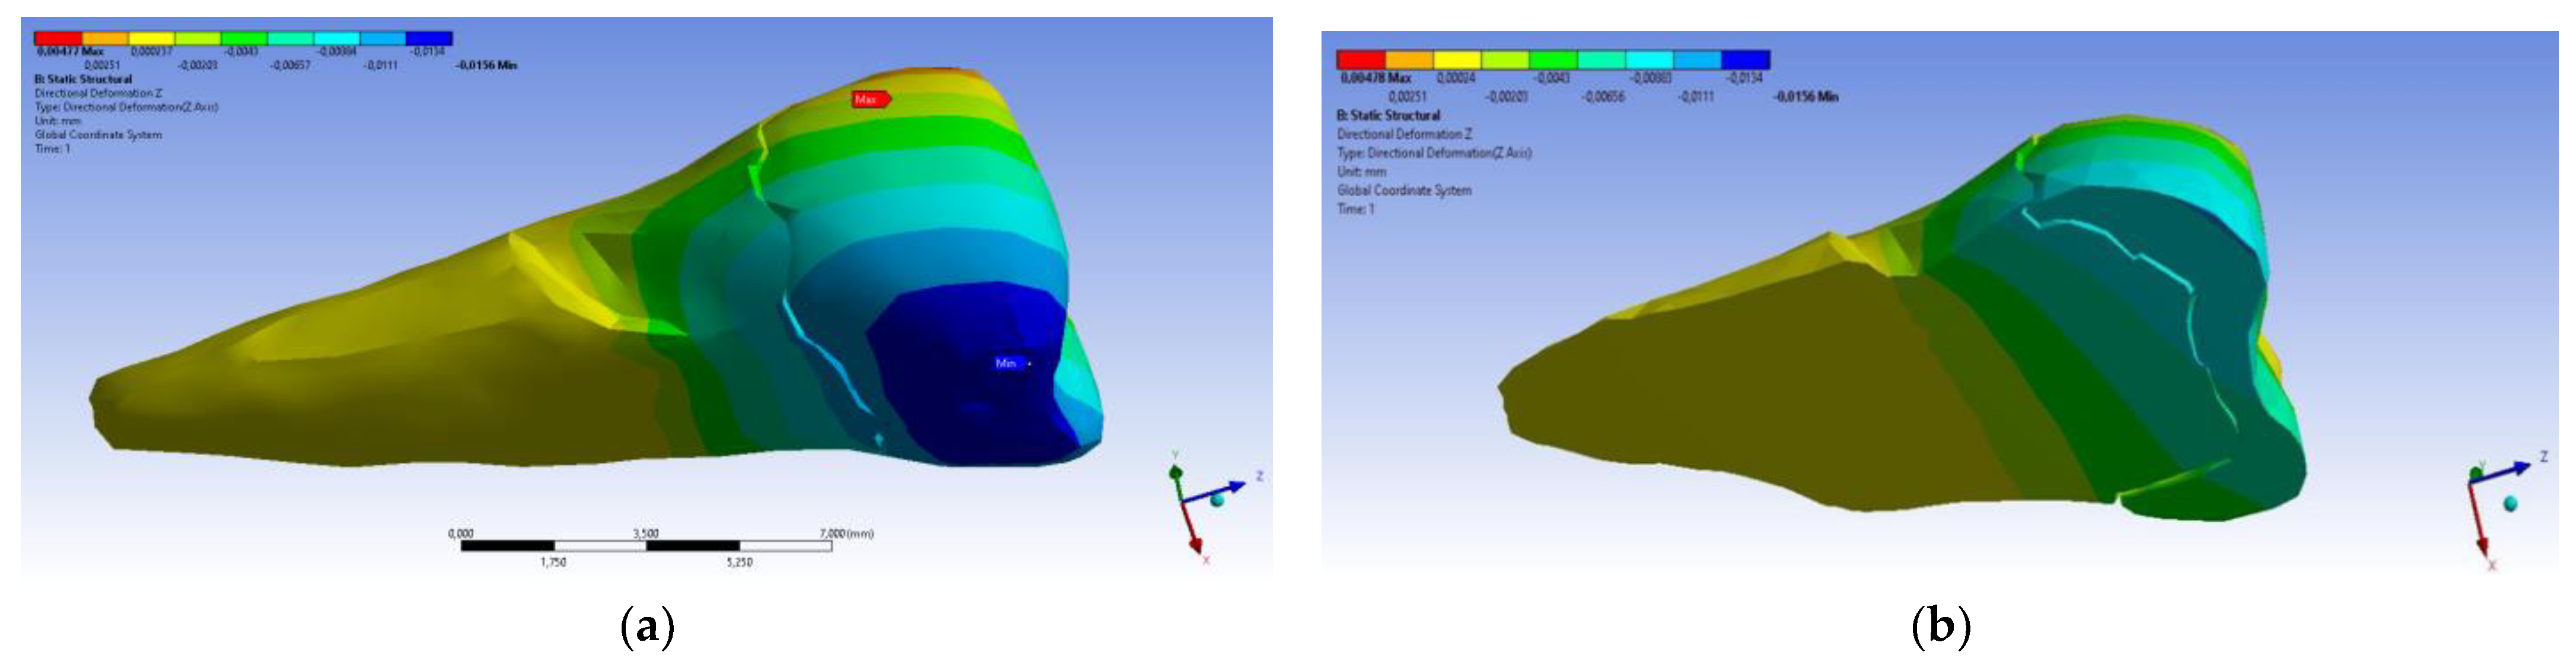

3. Finite Element Analysis (FEA) of Mandibular Right Premolars

| Total Deformation | Deformation in X Direction | Deformation in Y Direction | Deformation in Z Direction | Equivalent Stress | Normal Stress X | Normal Stress Y | Normal Stress Z | Maximum Main Stress | Minimum Main Stress | Tangential Stress XY | Tangential Stress YZ | Tangential Stress XZ | |

|---|---|---|---|---|---|---|---|---|---|---|---|---|---|

| Minimum | 0 mm | −4.24 × 10−3 mm | −2.52 × 10−2 mm | −1.56 × 10−2 mm | 1.01 × 10−6 MPa | −35.6 MPa | −57.1 MPa | −104 MPa | −15.2 MPa | −152 MPa | −43.7 MPa | −39.6 MPa | −56.3 MPa |

| Maximum | 2.77 × 10−2 mm | 3.57 × 10−3 mm | 6.98 × 10−4 mm | 4.78 × 10−3 mm | 248 MPa | 61.5 MPa | 177 MPa | 72.2 MPa | 195 MPa | 21.4 MPa | 44.2 MPa | 117 MPa | 22.2 MPa |

| Minim. in | Cementum | Cementum | Enamel | Enamel | Cementum | Cementum | Enamel | Enamel | Enamel | Cementum | Enamel | Enamel | Cementum |

| Maxim. in | Enamel | Enamel | Cementum | Enamel | Cementum | Enamel | Enamel | Enamel | Enamel | Enamel | Cementum | Cementum | Cementum |